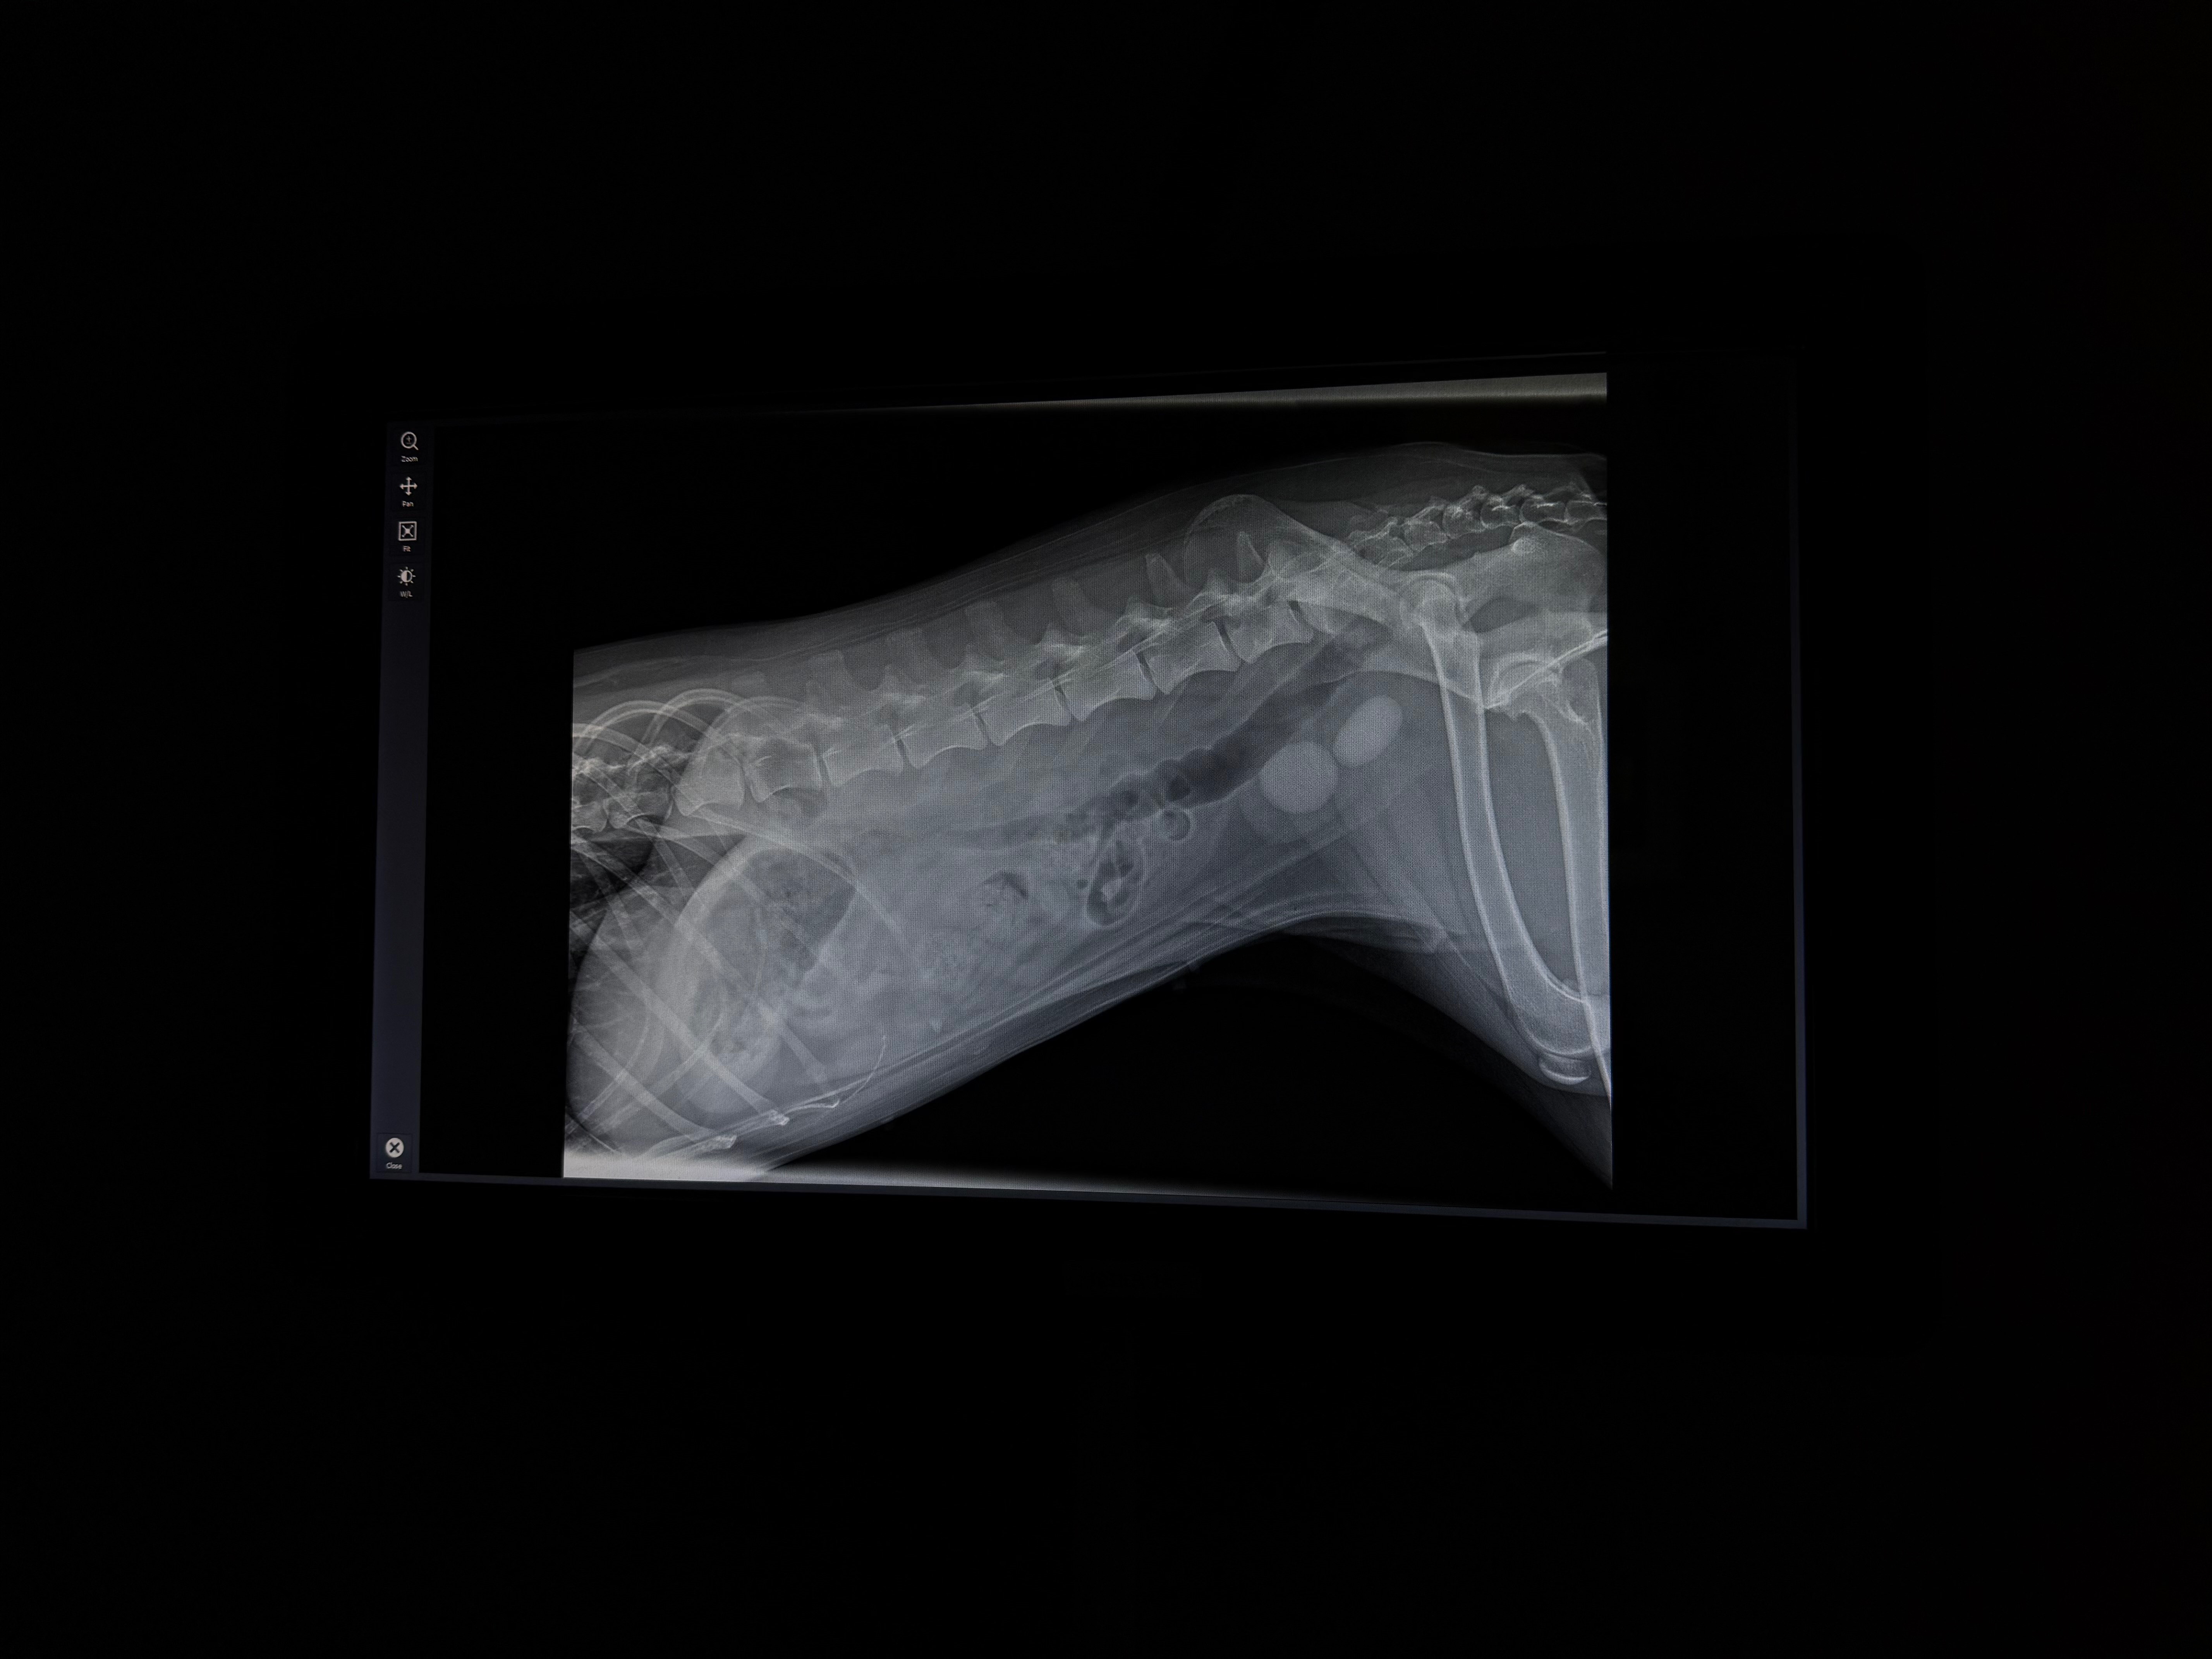

Venus the husky needs urgent surgery to remove bladder stones; funds cover operation

Hello friends, I don’t really know where to start. Many of you have met my sweet dog Venus, the most loving husky I know. This month we found out she has bladder stones that are too large to resolve with diet alone. She requires surgery to have them removed and it’ll cost around $1,500. She is currently struggling to use the bathroom and I can tell she is uncomfortable. Like many of the people I know, I’m barely making ends meet for just the basics. I know I will not be able to save enough to pay for this surgery in time for it to save her life. The longer I wait to have this done, the more damage the stones cause to her bladder and the more complicated it becomes. I struggle to ask for help, especially with finances. However, this sweet girl is my baby and it kills me to see her in pain. So if you can contribute in any way, it is appreciated beyond what words can express. Thank you for taking the time to read my words and learn about this troubling situation I’m in. Much love to you all.